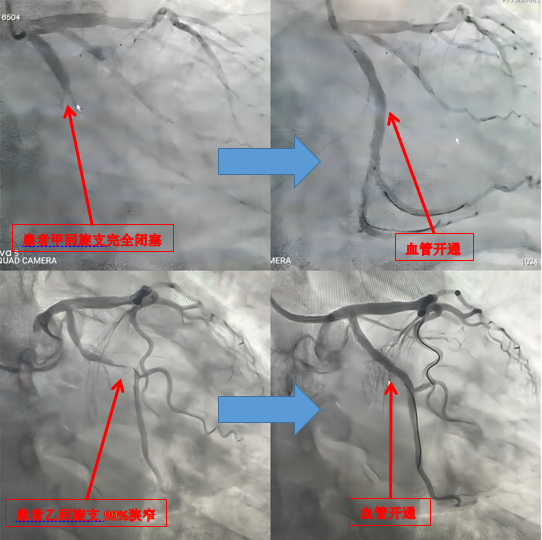

當(dāng)前位置:首頁(yè)>新聞中心>新聞動(dòng)態(tài)2月23日凌晨3點(diǎn),我院胸痛診室同時(shí)診治了兩名急性心肌梗死患者。時(shí)間就是生命,時(shí)間就是心肌,救治刻不容緩。胸痛中心立即啟動(dòng)院內(nèi)綠色通道,雙導(dǎo)管室同開(kāi)臺(tái),同時(shí)為兩名患者搭建救心“高速路”,兩名患者均繞行心內(nèi)科、CCU進(jìn)行了PCI術(shù)(經(jīng)皮冠狀動(dòng)脈介入治療),目前病情平穩(wěn)已渡過(guò)危險(xiǎn)期。